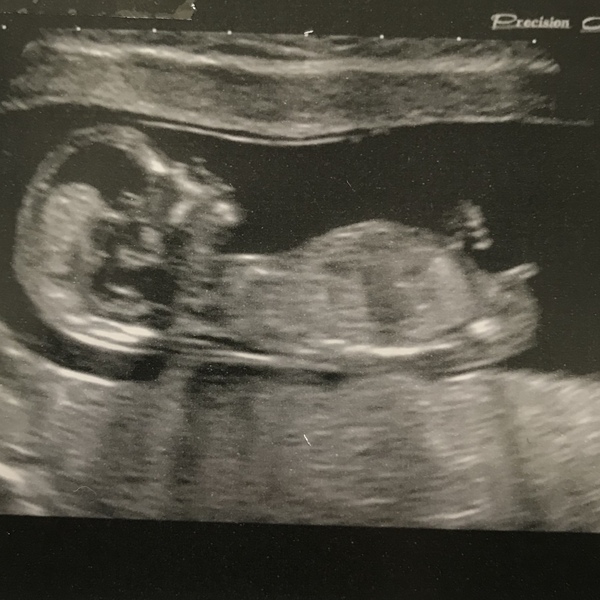

Hi again everyone, as a reminder I’m 32, DC#2, scan brought my due date forward 3 days to the 6th May. Scan went well although baby was really wriggling around so she sent me out to do half a wee to try and get at it from a different angle but didn’t have much luck! She got a decent pic at first though:

@catflapflapjack lovely scan picture